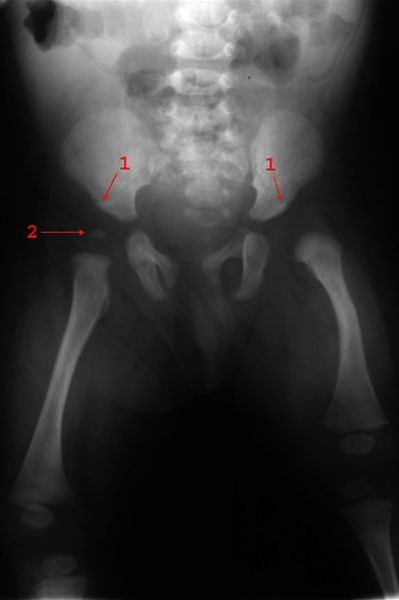

Venstresidig hofteledsdysplasi med stejl acetabulumvinkel, lateralisering af caput femoris og forsinket mineralisering af caputs knoglekerne.

1. Acetabularvinkel

2. Knoglekerne højre caput femoris (venstre er ikke mineraliseret)